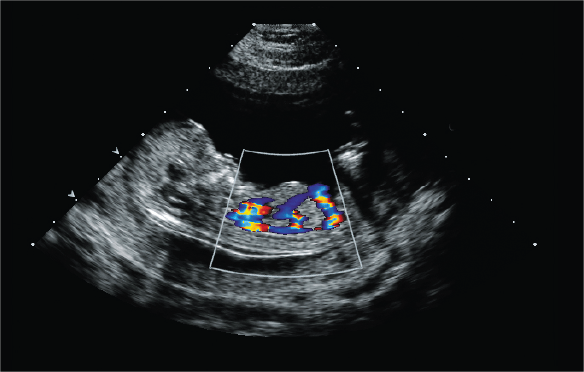

doppler

Healthcare professionals use ultrasounds to examine internal structures, such as bones and organs. They use a Doppler ultrasound

Healthcare professionals use ultrasounds to examine internal structures, such as bones and organs. They use a Doppler ultrasound.